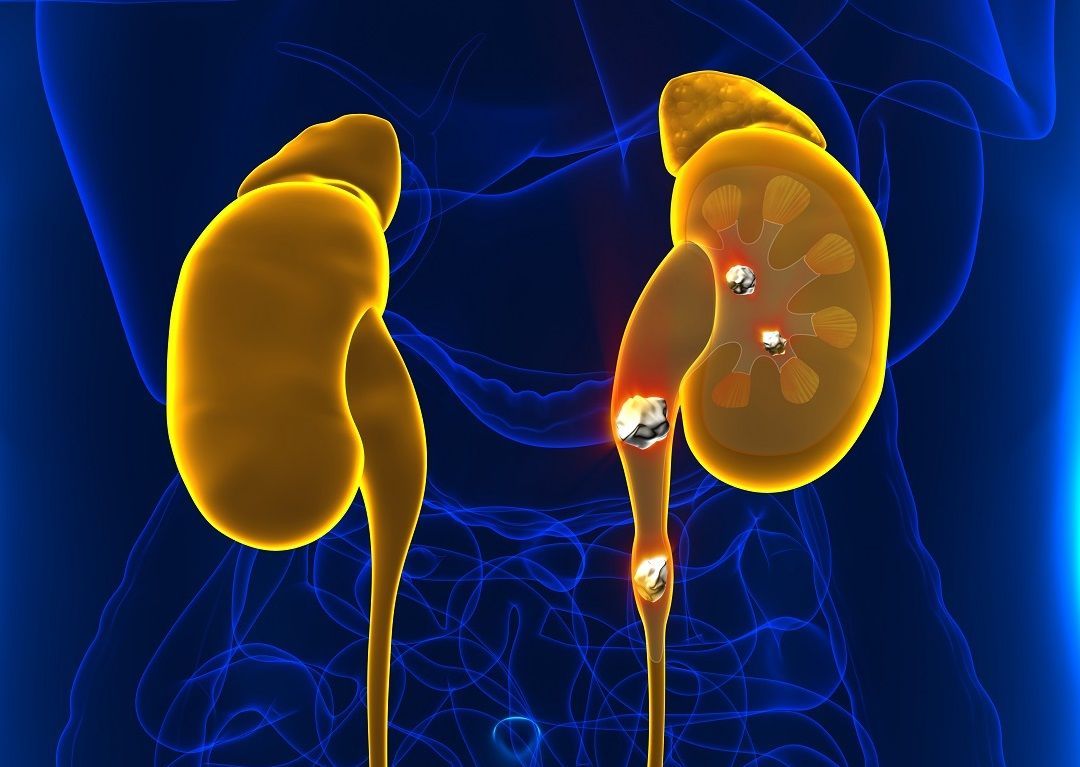

Η αύξηση της περιβαλλοντικής θερμοκρασίας, έχει οδηγήσει σε αύξηση των ανθρώπων που πάσχουν από νεφρολιθίαση.

Ειδικότερα, ολοένα και περισσότερες μελέτες δείχνουν ότι η νεφρολιθίαση επιδεινώνεται από τη ζέστη και την αφυδάτωση.

Οι ειδικοί εκτιμούν ότι τα περιστατικά θα αυξηθούν ακόμα περισσότερο τις επόμενες δεκαετίες, ακόμα κι αν ληφθούν μέτρα για να μειωθούν οι εκπομπές των ρύπων.

Υπολογίζεται ότι πλέον ένας στους 10 ανθρώπους αναπτύσσουν νεφρολιθίαση κάποια στιγμή στη ζωή τους, με τον αριθμό των κρουσμάτων να είναι υψηλότερος στις νοτιότερες περιοχές του δυτικού ημισφαιρίου, απ’ ό,τι στις βορειότερες.

Τα περιστατικά παρουσιάζουν επίσης εποχιακή διακύμανση (είναι περισσότερα το καλοκαίρι απ’ ό,τι τον χειμώνα), ενώ μέχρι πριν από δύο δεκαετίες ήταν εμφανώς περισσότερα μεταξύ των ανδρών.

Νεότερα δεδομένα, όμως, δείχνουν ότι το χάσμα μεταξύ των φύλων, αλλά και των ηλικιών μειώνεται.

Ανάλυση που δημοσιεύτηκε το 2021 στις ΗΠΑ, έδειξε ότι ο επιπολασμός της νεφρολιθίασης αυξήθηκε στις γυναίκες από 6,5% την περίοδο 2007-2008, σε 9,4% την περίοδο 2017-2018, προσεγγίζοντας σημαντικά τον αντίστοιχο επιπολασμό στους άνδρες (ήταν 10,9%).

Ανάλογα ευρήματα είχαν μελέτες και στους εφήβους, με τα αυξανόμενα περιστατικά παχυσαρκίας να θεωρούνται σημαντικός παράγοντας.

Την κατάσταση επιβαρύνει ακόμα περισσότερο η κλιματική αλλαγή που προκαλεί ολοένα περισσότερα κύματα καύσωνα.

Ερευνητικές ομάδες σε ΗΠΑ και Ευρώπη έχουν δημοσιεύσει μελέτες που δείχνουν ότι σε διάστημα 2-20 ημερών από ένα κύμα καύσωνα, αυξάνονται αισθητά τα περιστατικά νεφρολιθίασης. Έχει επίσης υπολογιστεί ότι ο κίνδυνος σχηματισμού πέτρας στο νεφρό αυξάνεται κατά 4% με κάθε αύξηση της θερμοκρασίας κατά 1 βαθμό Κελσίου πάνω από το φυσιολογικό για την εποχή σε έναν τόπο.

Επιστήμονες από τη Φιλαδέλφεια, εξάλλου, υπολόγισαν ότι μέχρι το τέλος του αιώνα τα περιστατικά νεφρολιθίασης θα έχουν αυξηθεί από 2,2% έως σχεδόν 4% αναλόγως με το αν θα μειωθούν οι εκπομπές ρύπων σε ένα μέτριο επίπεδο ή θα παραμείνουν ως έχουν.

Η νεφρολιθίαση είναι μία από τις συχνότερες παθήσεις του ουροποιητικού στον δυτικό κόσμο και προκαλεί σοβαρή νοσηρότητα στους ασθενείς.

Οι λίθοι σχηματίζονται όταν ορισμένες από τις ουσίες που αποβάλλονται στα ούρα (π.χ. ασβέστιο, οξαλικά άλατα, φωσφορικά άλατα) βρίσκονται σε μεγάλες συγκεντρώσεις και στο κατάλληλο περιβάλλον ούρων, με αποτέλεσμα την κρυσταλλοποίησή τους.

Ένας λίθος διαμέτρου κάτω των 4 χιλιοστών μπορεί να χρειαστεί 1-2 εβδομάδες για να διέλθει στον ουρητήρα και στην ουροδόχο κύστη, για να αποβληθεί από τον οργανισμό. Ένας μεγαλύτερος λίθος μπορεί να χρειασθεί 2-3 εβδομάδες, προκαλώντας στην πορεία συμπτώματα όπως πόνο, αιματουρία και ουρολοίμωξη.

Ο πόνος εκδηλώνεται όταν ένας λίθος δυσκολεύεται λόγω μεγέθους και μορφολογίας να διέλθει από τον ουρητήρα για να φτάσει στην ουροδόχο κύστη. Αν, όμως, εγκλωβιστεί στον ουρητήρα και τον αποφράξει, τότε μπορεί να προκληθεί υδρονέφρωση (διάταση του ουρητήρα και του νεφρού) επειδή διακόπτεται η διοχέτευση των ούρων.

Η υδρονέφρωση προκαλεί αιφνίδιο σπασμό και ακραίο πόνο στη νεφρική χώρα, που είναι γνωστός ως κολικός του νεφρού. Ο πόνος αυτός συχνά συνοδεύεται από μικρή ή μεγάλη αιματουρία, ναυτία και έμετο.

Η διάμεση ηλικία εμφάνισης της νεφρολιθίασης για πρώτη φορά είναι τα 30-40 έτη για τους άνδρες και τα 35-55 έτη για τις γυναίκες, αλλά είναι πολύ συχνή και σε νεότερα άτομα. Σε μία στις δύο περιπτώσεις, οι λίθοι υποτροπιάζουν μέσα σε 5-10 χρόνια, ενώ στο 75% των περιπτώσεων υποτροπιάζουν μέσα σε μία 20ετία.

Πρόληψη

Η ανάπτυξη έστω και μικρής αφυδάτωσης οδηγεί σε μείωση της παραγωγής των ούρων. Η μείωση στον όγκο τους έχει ως συνέπεια να αυξάνεται η συγκέντρωση των μεταλλικών στοιχείων, γεγονός που ευνοεί την ανάπτυξη των λίθων.

Η πολύ καλή ενυδάτωση του οργανισμού είναι ο αποτελεσματικότερος τρόπος πρόληψης της νεφρολιθίασης. Συνιστάται κατανάλωση τουλάχιστον 1,5 λίτρου υγρών σε καθημερινή βάση, όλες τις εποχές του χρόνου. Όταν έχει ζέστη, η ποσότητα αυτή πρέπει να αυξάνεται κατά τουλάχιστον 1 λίτρο.